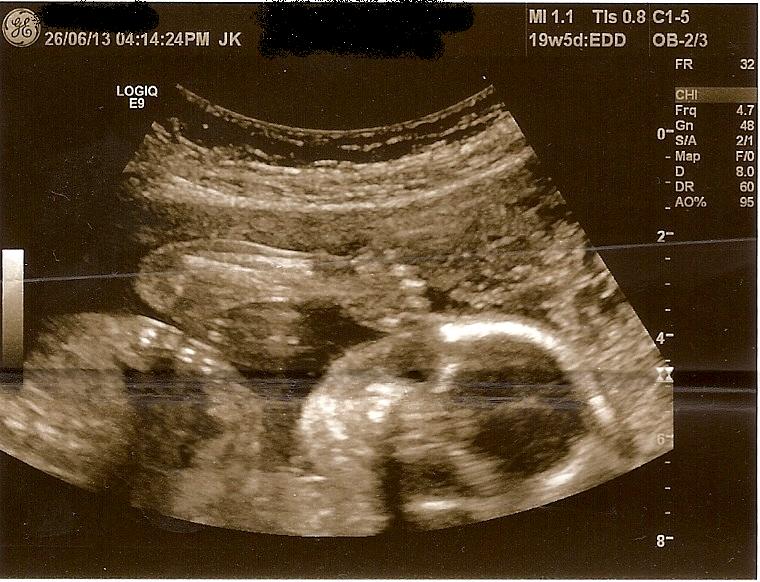

Please help girl or boy skull theory